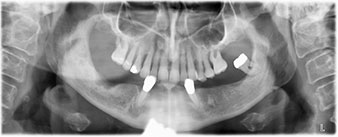

The 64-year-old patient presented with residual dentition of teeth 38, 33 and 43 and a clasp denture in the mandible (Fig. 1 and 2).

A three-dimensional cone beam computed tomography scan (CBCT, Planmeca) was performed to aid planning and minimize risks. This revealed that the quality and quantity of the available bone were sufficient for the surgery and immediate restoration using the Fast & Fixed method. Following the protocol for this concept, the implants are inserted at 35, 32, 42 and 45. Angling the distal implants by up to 45° shifts the emergence profile to posterior and generates a larger support polygon (Fig. 3).